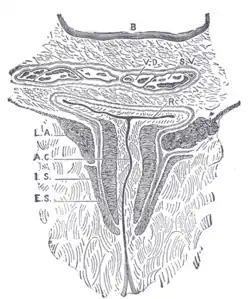

Coronal section through the anal canal. B. Cavity of urinary bladder V.D. Ductus deferens. S.V. Seminal vesicle. R. Second part of rectum. A.C. Anal canal. L.A. Levator ani. I.S. Sphincter ani internus. E.S. Sphincter ani externus. | |

The anal canal is the part that connects the rectum to the anus, located below the level of the pelvic diaphragm.[1] It is located within the anal triangle of the perineum, between the right and left ischioanal fossa. As the final functional segment of the bowel, it functions to regulate release of excrement by two muscular sphincter complexes. The anus is the aperture at the terminal portion of the anal canal.

In humans, the anal canal is approximately 2.5 to 4 cm (0.98 to 1.57 in) long, from the anorectal junction to the anus.[2][3][4] It is directed downwards and backwards. It is surrounded by inner involuntary and outer voluntary sphincters which keep the lumen closed in the form of an anteroposterior slit.

Relations

- The ischioanal fossa are on each side of the anal canal.

- The perianal space surrounds the anal canal below the white line.

- The submucous space of the canal lies above the white line between the mucous membrane and internal anal sphincter muscle.